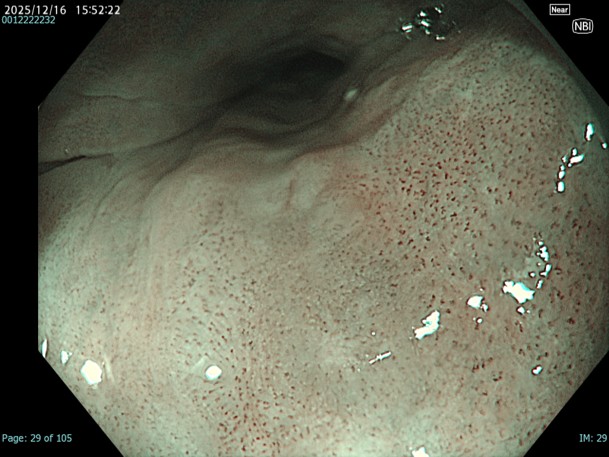

• NBI観察(近景)

強調設定:A8

図3 図4 図5

近景、拡大観察を行う事でIPCLとしては口径不同を伴ったB1血管を診断できる。一方で部位によってはA血管と判別が難しい部位もあり、また色調変化も周囲粘膜とモザイク様で判断が難しい部位も存在する。